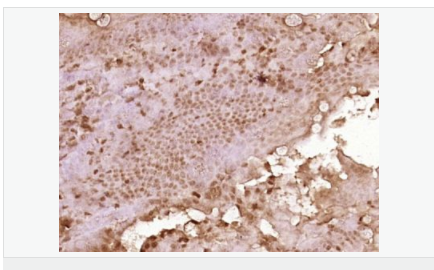

產品介紹C3orf32 (chromosome 3 open reading frame 32), also known as fls485, is a 353 amino acid protein encoded by a gene that maps to human chromosome 3p26.1. Chromosome 3 is made up of approximately 214 million bases encoding over 1,100 genes. Notably, there is a chemokine receptor gene cluster and a variety of human cancer related loci on chromosome 3. Particular regions of the chromosome 3 short arm are deleted in many types of cancer cells. Key tumor suppressing genes on chromosome 3 encode apoptosis mediator RASSF1, cell migration regulator HYAL1 and angiogenesis suppressor SEMA3B. Marfan Syndrome, porphyria, von Hippel-Lindau syndrome, osteogenesis imperfecta and Charcot-Marie-Tooth disease are a few of the numerous genetic diseases associated with chromosome 3.

Tissue Specificity:

Expressed in enterocytes of small and large intestinal mucosa (at protein level). Expressed in enterocytes, chromaffine and interstitial cells.